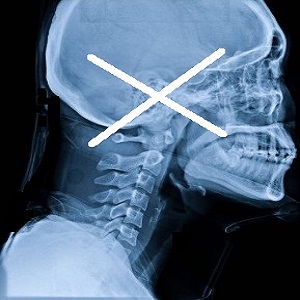

頸椎の位置でも顎関節の位置は変化

顎の解剖学について

下顎の動き

顎関節は肩や股関節と異なり左右の二つ

の関節からなり左図の関節円盤を超える

までは顎の動き(下アゴ)は転がりながら

すべり運動をしている訳であります。